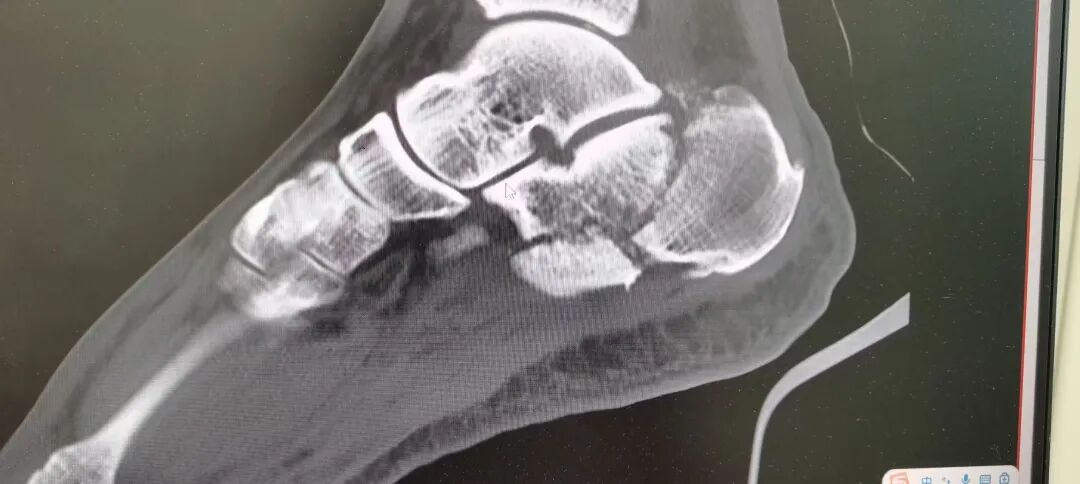

术后

我院骨四科开展的“跟骨微创撑开翘拨三步复位内固定术”,是针对跟骨骨折的一种治疗选择。该技术通过有限切口,利用特殊器械进行骨折复位与固定,旨在减小手术创伤,降低手术对局部软组织的影响。